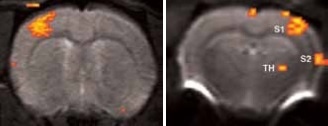

BOLD activation at 11.7 Tesla using the quadrature surface coil with a resolution of (left) 300 x 300 x 2000 μm3 for high quality and (right) 150 x 200 x 2000 μm3 for high sensitivity.

Figure 2. BOLD activation at 11.7 Tesla using the quadrature surface coil with a resolution of (left) 300 x 300 x 2000 μm3 for high quality and (right) 150 x 200 x 2000 μm3 for high sensitivity. Image Credit: Bruker BioSpin Group

Using older DBX electronics and linear surface coils at 7.0 Tesla, BOLD contrast with 400 x 400 x 2000 μm3 resolution can be obtained. Combined with T2-maps, loss of functional activity and its instant recovery as well as stroke lesion (Figure 1) was defined[4,5]. A combination of faster AVANCE II readout electronics, quadrature surface coil, and higher field strength of 11.7 Tesla increased both resolution and SNR to less than 200 x 200 x 2000 μm3, which is more than sufficient to identify the tiny structures along the neuronal activity pathway like the thalamus and secondary somatosensory cortex S2 (Figure 2) with BOLD contrast.

When the forepaw is electrically stimulated, the thalamus, and primary (S1) and secondary (S2) somatosensory corte are activated. To achieve this, electrical pulses (1–2 mA of 0.3 ms duration, at 6 or 3 Hz) are applied for 15 seconds after a resting period of 45 seconds, repeated 5 times. It takes 5 minutes and 45 seconds for the resultant total scan.